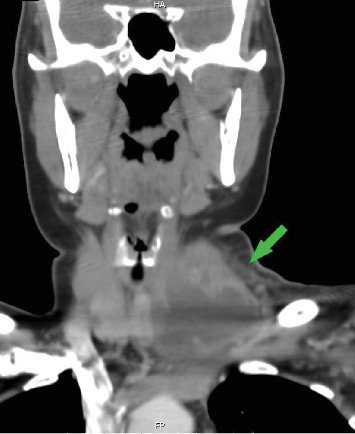

This case report discusses a rare instance of acute granulomatous thyroiditis resulting from brucellosis. A 47-year-old female cattle farmer presented with painful neck swelling and systemic symptoms. Initial investigations suggested a potential malignancy, but further testing, such as serological tests, pathology and imaging revealed brucellosis as the underlying cause. The patient underwent surgical intervention for abscess drainage and antibiotic therapy for brucellosis and showed significant clinical improvement. This case underscores the need for awareness of Brucella melitensis, a zoonotic infection, as a differential diagnosis in thyroid conditions, contributing to the understanding of its varied manifestations and complications, especially in endemic regions.